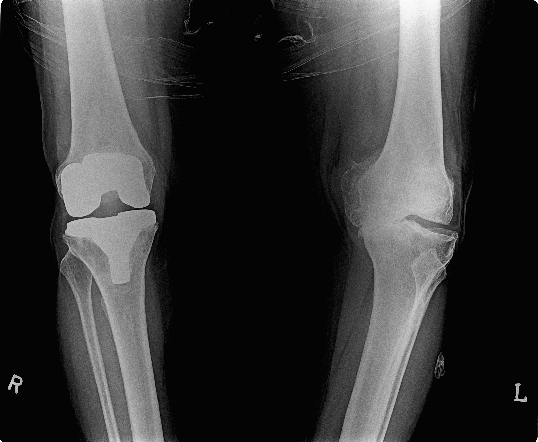

knee replacement

Knee replacement surgery (arthroplasty) is a routine operation that involves replacing a damaged, worn or diseased knee with an artificial joint.

Adults of any age can be considered for a knee replacement, although most are carried out on people between the ages of 60 and 80. More people are now receiving this operation at a younger age. A replacement knee usually lasts over 20 years, especially if the new knee is cared for properly and not put under too much strain. When a knee replacement is needed

Knee replacement surgery is usually necessary when the knee joint is worn or damaged to the extent that your mobility is reduced and you experience pain even while resting.

You can be make to walk or you can work with walker on second day after surgery . After one week you can walk normally without any support.